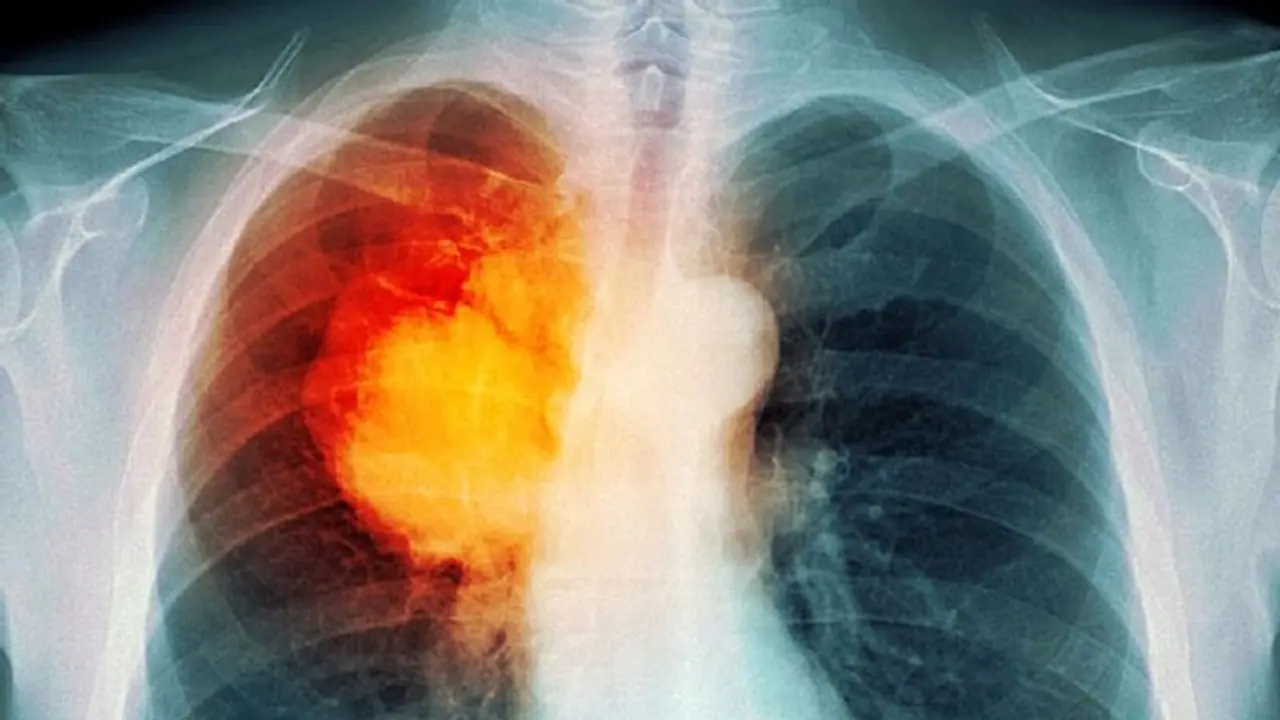

ലോകത്ത് തന്നെ വര്ധിച്ചുവരുന്ന രോഗങ്ങളുടെ പട്ടികയില് മുന്പന്തിയിലാണ് ശ്വാസകോശ അര്ബുദം അഥവാ 'ലംഗ് ക്യാന്സര്'. കണക്കുകള് പ്രകാരം 2018ല് മാത്രം പത്തര ലക്ഷത്തിലധികം പേരാണ് ശ്വാസകോശ അര്ബുദത്തെ തുടര്ന്ന് മരിച്ചതായി റിപ്പോര്ട്ടുകളിലുള്ളത്. ഇരുപത് ലക്ഷത്തിലധികം പേര്ക്ക് 'ലംഗ് ക്യാന്സര്' പിടിപെട്ടതായും റിപ്പോര്ട്ടുകള് സൂചിപ്പിക്കുന്നു.

ശ്വാസകോശ അര്ബുദം ബാധിക്കപ്പെട്ട് മരിക്കുന്നവരില് അധികം പേരുടെ കേസുകളിലും അവര്ക്ക് തിരിച്ചടിയായിരിക്കുന്നത് രോഗം കണ്ടെത്താന് വൈകി എന്നതായിരിക്കും. ഇക്കാര്യം ഡോക്ടര്മാര് തന്നെ സാക്ഷ്യപ്പെടുത്തുകയും ചെയ്യുന്നു.

ആദ്യഘട്ടത്തിലാണ് ശ്വാസകോശ അര്ബുദം കണ്ടെത്തുന്നത് എങ്കില് ഫലപ്രദമായ ചികിത്സയിലൂടെ രോഗത്തെ അതിജീവിക്കാനാകുമെന്നാണ് ഡോക്ടര്മാര് വ്യക്തമാക്കുന്നത്. കീമോതെറാപ്പി, സര്ജറിറേഡിയോ തെറാപ്പി തുടങ്ങി പല തരത്തിലാണ് 'ലംഗ് ക്യാന്സര്'നുള്ള ചികിത്സകള്.

എന്നാല് പലപ്പോഴും രോഗികള് ചികിത്സ തേടിയെത്തുന്ന സമയം വൈകുന്നതാണ് വലിയ പ്രതിസന്ധിയാകുന്നത്. ശ്വാസകോശ അര്ബുദം മൂലമുള്ള മരണനിരക്ക് വര്ധിക്കുന്നതിന്റെ ഏക കാരണവും രോഗം കണ്ടെത്താന് വൈകുന്നു എന്നത് തന്നെയാണ്.